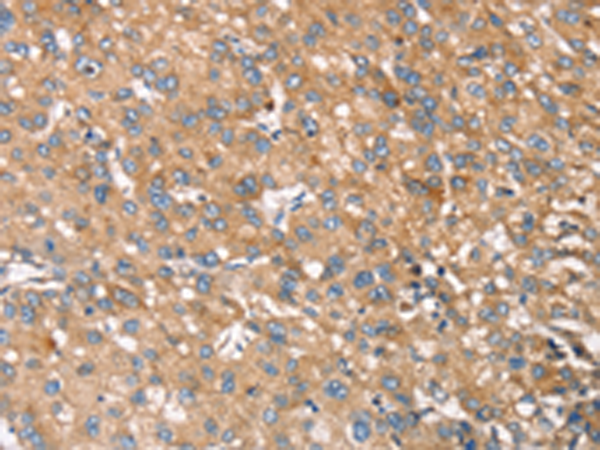

分类: 科研抗体货号: P08712别名: ARA54; HFB30; TRIAD2; HRIHFB2038应用: WB,IHC反应种属: Human, Mouse